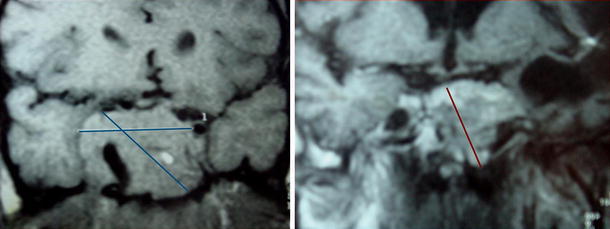

Fig. 1.

MRI scans of pituitary tumor at diagnosis (December 1994, left) and 9 years after surgery and radiotherapy without medical treatments (January 2008, right)

| Voluminous sellar mass with sphenoid sinus invasion, extension in the suprasellar cistern causing displacement of the pituitary stalk and invasion into the right cavernous sinus (Fig. 1) |

| For MRI scan in Jan 2008, 9 years after surgery and radiotherapy without medical treatments, see Fig. 1 |